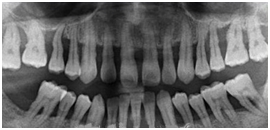

患者女性,59歲,右側(cè)后牙咀嚼無力,刷牙時(shí)牙齦出血。無系統(tǒng)性疾病??谇粰z查顯示全口多數(shù)牙牙石(++),牙齦紅腫,探診出血,牙周袋袋深4——6mm,右下后牙有Ⅰ——Ⅱ度松動(dòng),X線片如圖所示: